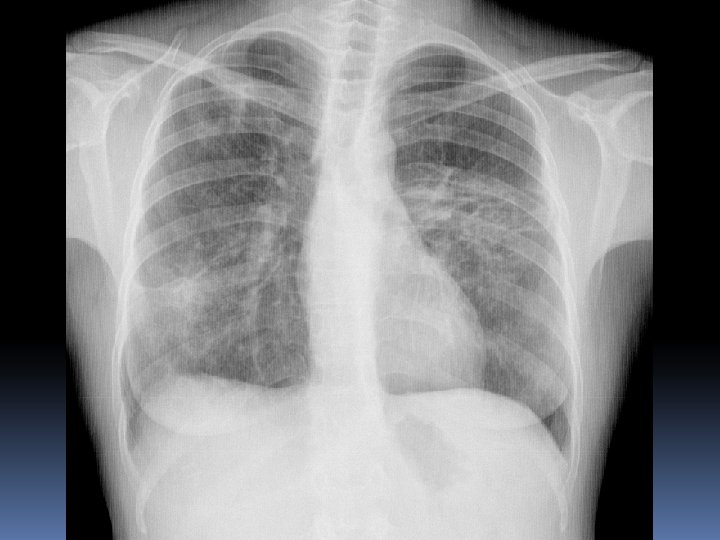

5 años mas tarde……….

2008 2013